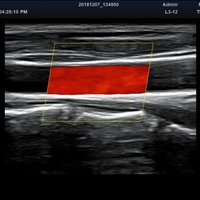

Anwendungsbereiche Abdomen MSK, Nerven, Karotis, periphere Gefäße, Schilddrüse, Mamma

Bildgebungs-Modi B-Modus, CF, M, PW, PD B-Modus, CF, M, PW, PD

• Farbdoppler: farbige Darstellung der Richtung des Blutflusses